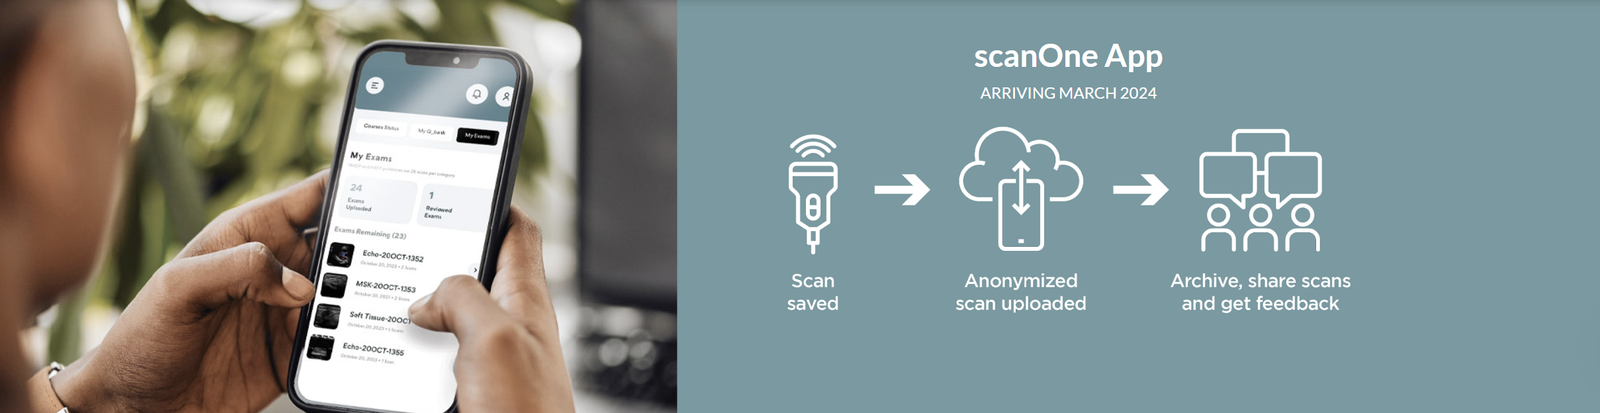

Coming in March – GUSI’s scanOne™ App!

GUSI’s scanOne™ mobile app offers a fast, secure, HIPAA-compliant solution to anonymize and upload POCUS images from any ultrasound device. The scanOne app ensures accuracy and data integrity, to support sharing scans for QA and credentialing. Learn more.